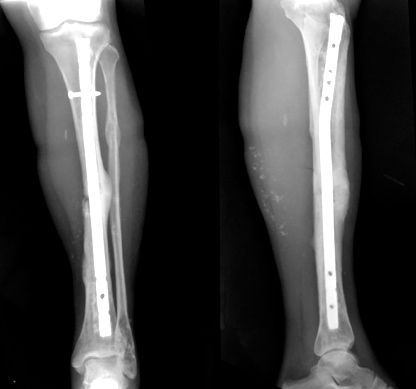

Se realizó una nueva biopsia ante la persistencia radiológica de las imágenes patológicas, que no evidenció tejido tumoral. En la evolución la paciente presentó una fractura patológica en el lugar de la biopsia, por la cual se realizó un enclavijado endomedular (Figura 2). El material del fresado endomedular fue analizado y la anatomía atológica no evidenció células tumorales.

Figura 2: Radiografías de la paciente con fractura consolidada y buena alienación. Lesiones líticas en el maleolo externo.